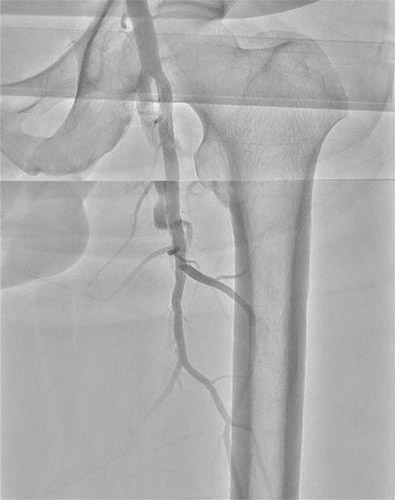

主訴は跛行(Rutherford分類3)の方で ABI検査を実施したところ0.62と低値。リスクファクターとして糖尿病(DM)、高血圧(HT)、脂質異常症(DL)が認められた。今回の標的病変は左大腿動脈(Lt. SFA CTO)【図1・図2】であり、アプローチ部位はTAI(Trans ankle intervention)にて施行することとした。

BKについてはATAは開存しており、PTAが途中から閉塞していることを確認した。【図3】